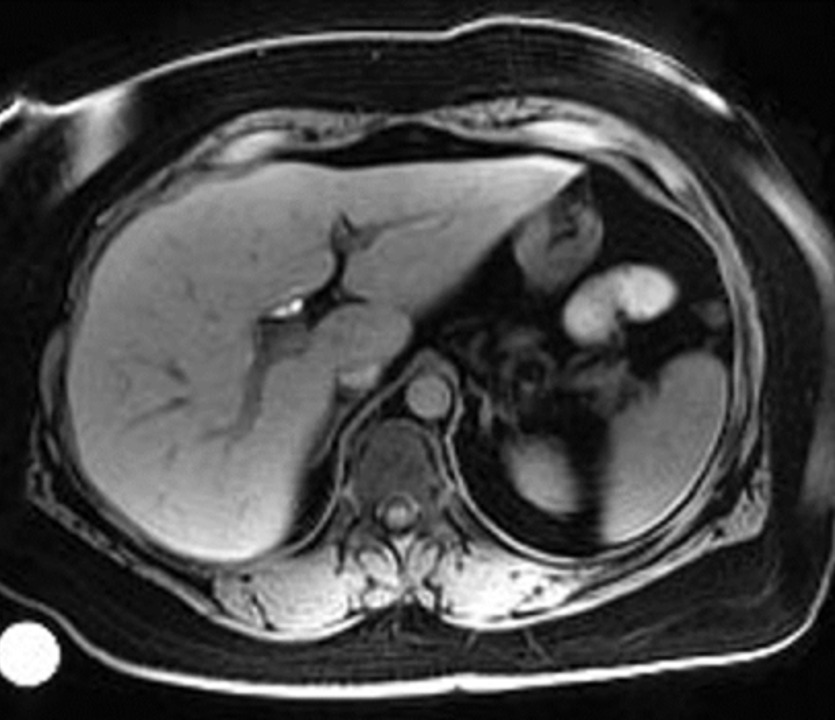

Imaging insights for body composition, muscle changes, and other end-organ effects to be discussed at GLP-1-Based Therapeutics Summit

Ground-breaking imaging for drug development is at the heart of what we do. Equally important is our extensive expertise in drug development and disease biology. This important mix of capabilities allows us to discuss and advise on study-design and to deliver clinical imaging studies addressing relevant biology.